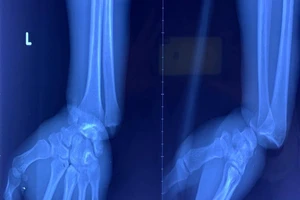

Cọng kẽm cuộn chặt cổ tay do buồn ngủ vì làm suốt ngày